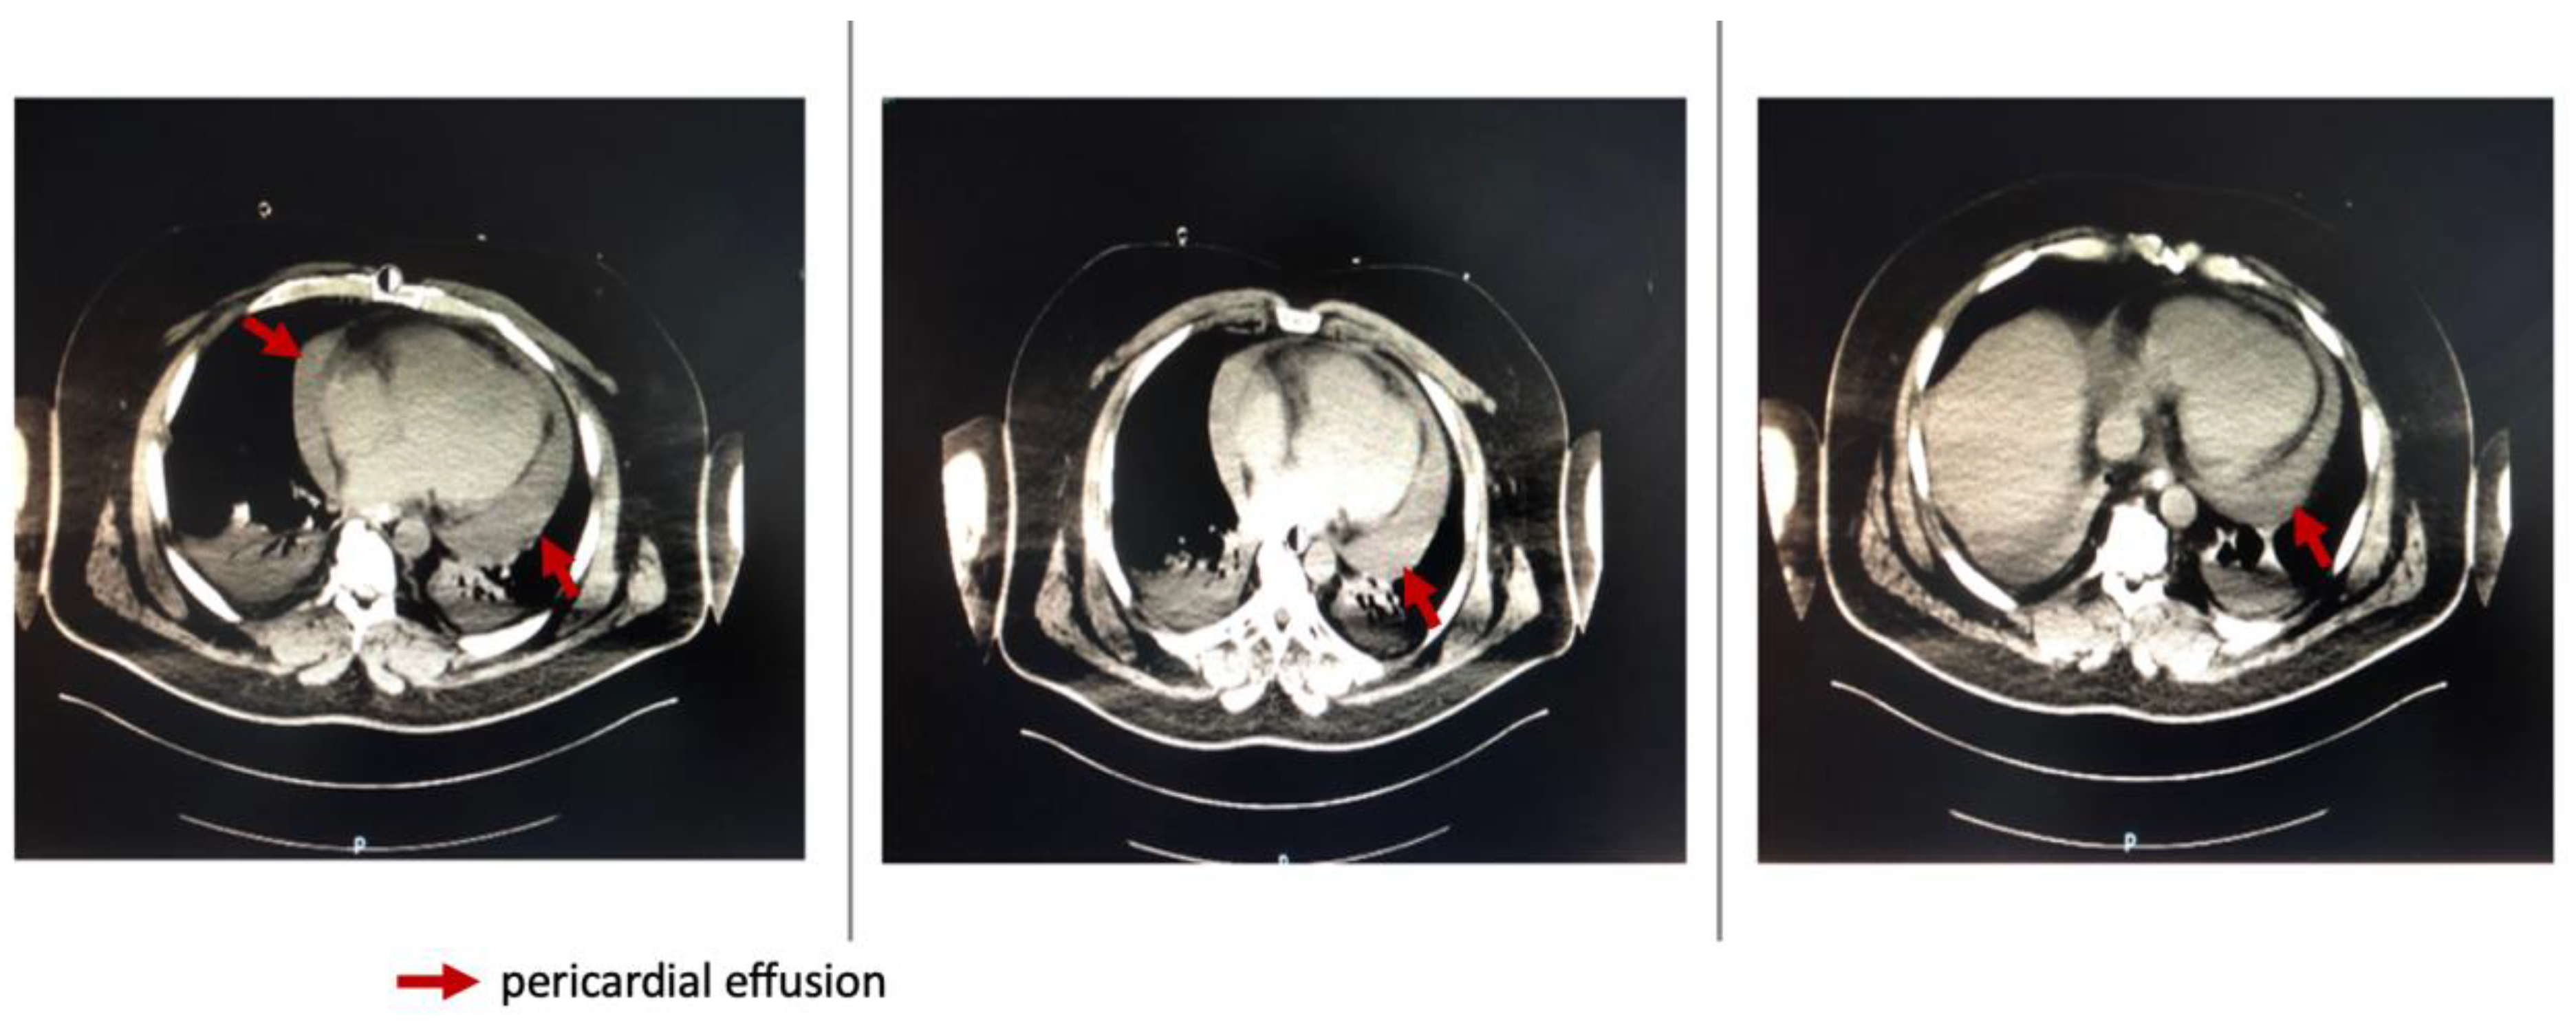

Repeated thoracic CT displayed significant circumferential pericardial effusion adjacent to the left ventricle and minimal bilateral pleural effusion (Figure 1).

Figure 1. Thoracic CT showing circumferential pericarditis.